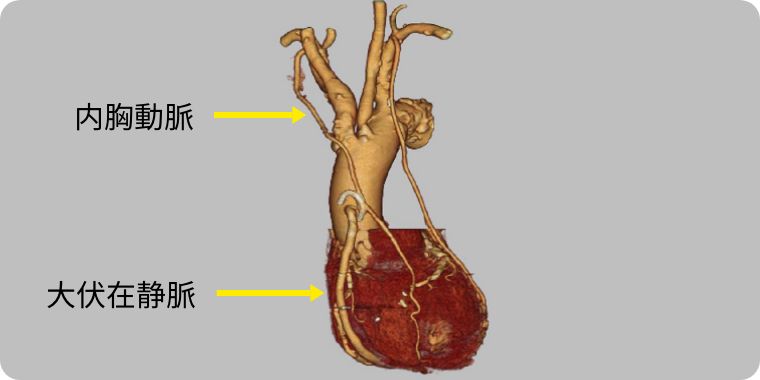

狭心症や心筋梗塞で、狭くなったり詰まった血管の先に新しい血管(グラフト)をつなぎ、血流の迂回路(バイパス)をつくる手術が冠動脈バイパス手術(CABG)です。

バイパスには基本的に以下の血管(グラフト)を使用します。最も重要な冠動脈である左前下行枝には、主に長期開存性に優れた内胸動脈をグラフトに使用します。その他の冠動脈についてはグラフトを組み合わせてバイパスのデザインを行います。

当院では、長期成績が良好と言われる両側の内胸動脈を積極的に使用しています。